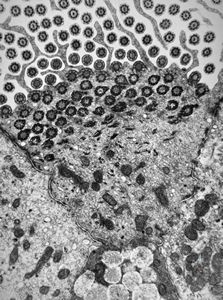

F,49y. | normal kinocilium - bronchus

F,5y. | immotile cilia syndrome - trachea

F,5y. | immotile cilia syndrome - rootlet of kinocilia